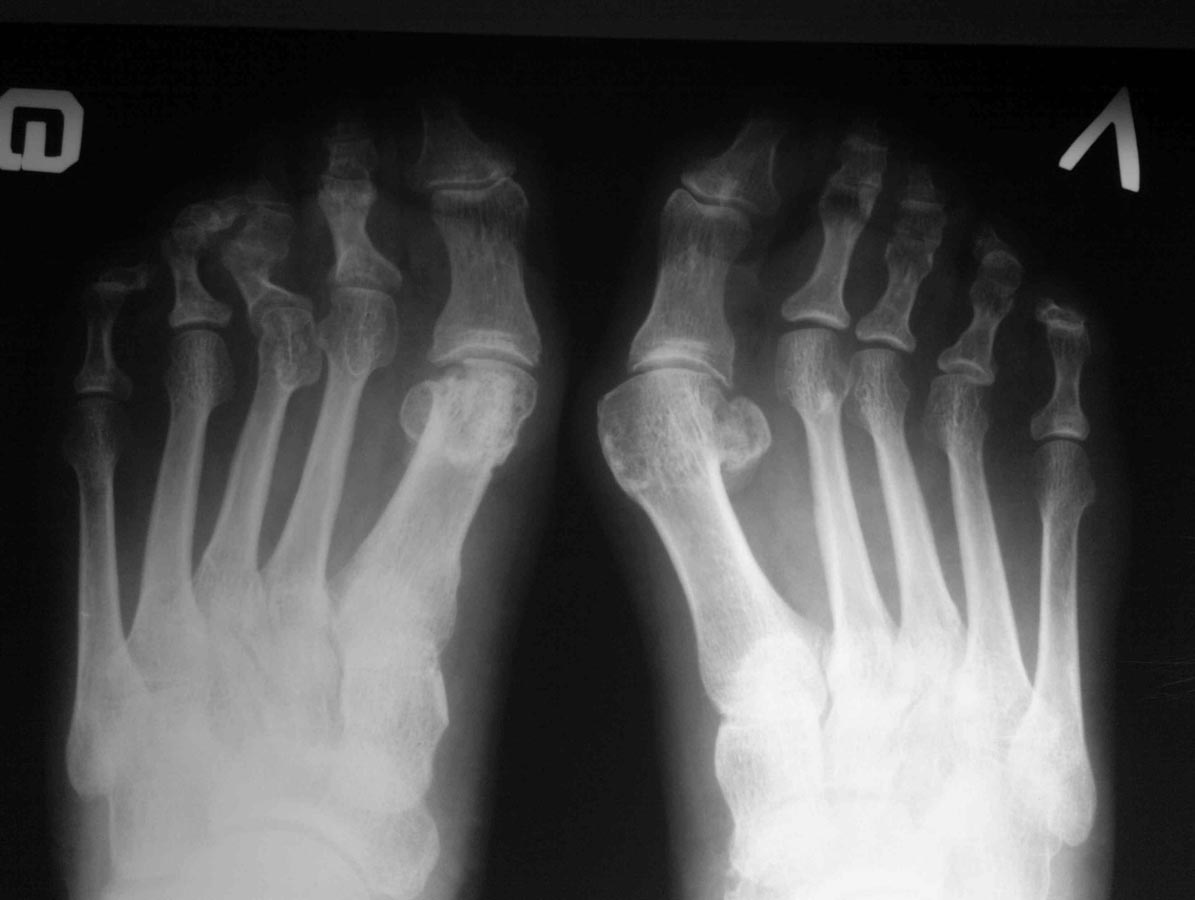

Уважаемые коллеги, обратилась пациентка 55 лет, оперированная около 3-х лет назад в одном из медицинских центров.

Операция, видимо, Logroscino справа, похоже, что с аваскуляром головки. Жалоб на первый луч особо не предьявляет, основное беспокойство - молоткообразные 2-3 пальцы, выраженная боль при ходьбе в проекции головок 2-3 плюсневых, омозолелость по подошвенной поверхности. Что на ваш взгляд целесообразно предпринять в данном случае:1.резекция головок с/ф с фиксацией спицей, возможно с Z- пластикой сухожилий разг.?

Сожалею, но других фото в ближайшее время не будетPS Левая стопа недавно оперирована у нас (SCARF), пациентка довольна